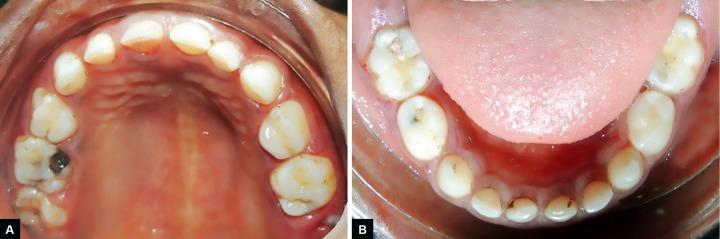

儿童原发性牙列局限性侵袭性牙周炎(LAP)是一种罕见疾病。LAP的主要特征是牙周袋深、骨质丧失、牙齿松动,有时还会出现牙齿自行脱落。LAP仅累及某些特定牙齿。Glanzmann血小板无力症(GT)是一种罕见的常染色体隐性出血性疾病。本文旨在介绍一名患有GT并出现LAP的5岁女孩病例,并讨论其临床管理。Prud'homme T、Roy E、Soueidan A、Fouassier M、Dajean-Trutaud S、Badran Z。一名患有Glanzmann血小板无力症的儿童诊断为局限性侵袭性牙周炎的多学科临床管理。《国际临床儿科牙科学杂志》2018年;11(4):344 - 348。

https://cdn.ncbi.nlm.nih.gov/pmc/blobs/4425/6212666/497eb2cbde32/ijcpd-11-344-g006.jpg

https://cdn.ncbi.nlm.nih.gov/pmc/blobs/4425/6212666/5e4481c32f3e/ijcpd-11-344-g001.jpg

https://cdn.ncbi.nlm.nih.gov/pmc/blobs/4425/6212666/63e579b8fce2/ijcpd-11-344-g002.jpg

https://cdn.ncbi.nlm.nih.gov/pmc/blobs/4425/6212666/530188dd4b5e/ijcpd-11-344-g003.jpg

https://cdn.ncbi.nlm.nih.gov/pmc/blobs/4425/6212666/ae98d286f7b0/ijcpd-11-344-g004.jpg

https://cdn.ncbi.nlm.nih.gov/pmc/blobs/4425/6212666/fd2a52a2b9fc/ijcpd-11-344-g005.jpg